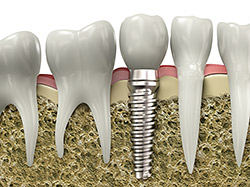

An implant is a synthetic tooth root in the shape of a post that is surgically placed into the jawbone. The “root” is usually made of titanium (the same material used in many replacement hips and knees), a metal that is well suited to pairing with human bone. A replacement tooth is then fixed to the post. The tooth can be either permanently attached or removable. Permanent teeth are more stable and feel more like natural teeth.

Single or Multiple Implants

implantsImplants are versatile. If you are only missing one tooth, one implant plus one replacement tooth will do the trick. If you are missing several teeth in a row, a few strategically placed implants can support a permanent bridge (a set of replacement teeth). Similarly, if you have lost all of your teeth, a full bridge or full denture can be permanently fixed in your mouth with a strategic number of implants.